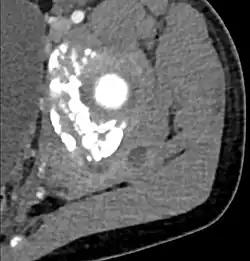

CT exam showing a multiloculated fluid collection in the left gluteus minimus muscle found to be a staph aureus pyomyositis in a 12-year-old healthy boy.

Coronal T2 weighted fat suppressed image showing a multiloculated fluid collection in the left gluteal musculature due to tropical pyomositis in a 12-year-old boy.